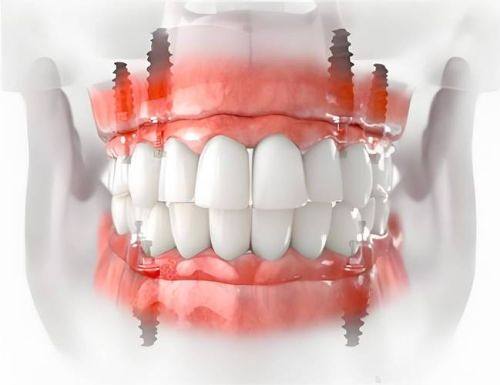

种植牙作为一种常见的牙齿修复方式,给众多缺牙患者带来了福音。一般来说,种植牙的寿命可以持续15年以上。不过,这并不是一个固定的数字,因为每个人的情况不同,种植牙的使用寿命也会有所差异。有些患者的种植牙可能使用了二三十年还依然完好,而有些患者的种植牙可能在几年后就出现了问题。这就需要我们了解影响其寿命的因素,从而尽可能延长种植牙的使用寿命。

种植牙质量和安装技术的影响

种植牙的质量和安装技术对其使用寿命有着至关重要的影响。高质量的种植体通常采用了精良的材料和工艺,具有良好的生物相容性和稳定性。它们能够更好地与牙槽骨结合,为种植牙提供坚实的基础。而优质的种植牙品牌在研发、生产和质量控制方面都有着严格的标准,能够确保种植体的质量和性能。

专精的安装技术也是确保种植牙成功的关键。经验多的牙科医生能够正确地将种植体植入到合适的位置,确保种植体与牙槽骨的紧密结合。在手术过程中,医生还会根据患者的具体情况,采取相应的措施,减少手术创伤,提高种植成功几率。所以,在选择种植牙时,一定要选择经验多的牙科医生和优质的种植牙品牌,这样才能提高种植成功几率,延长种植牙的使用寿命。